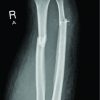

Tendo-achillis tenotomy is required as last stage of ponseti method of treatment of Congenital Talipes Equino Varus (CTEV). This technical note describes a simple method of doing a percutaneous tenotomy of tendo-achillis using a wide bore needle. This is a simple method and easy to learn and gives predictable results.